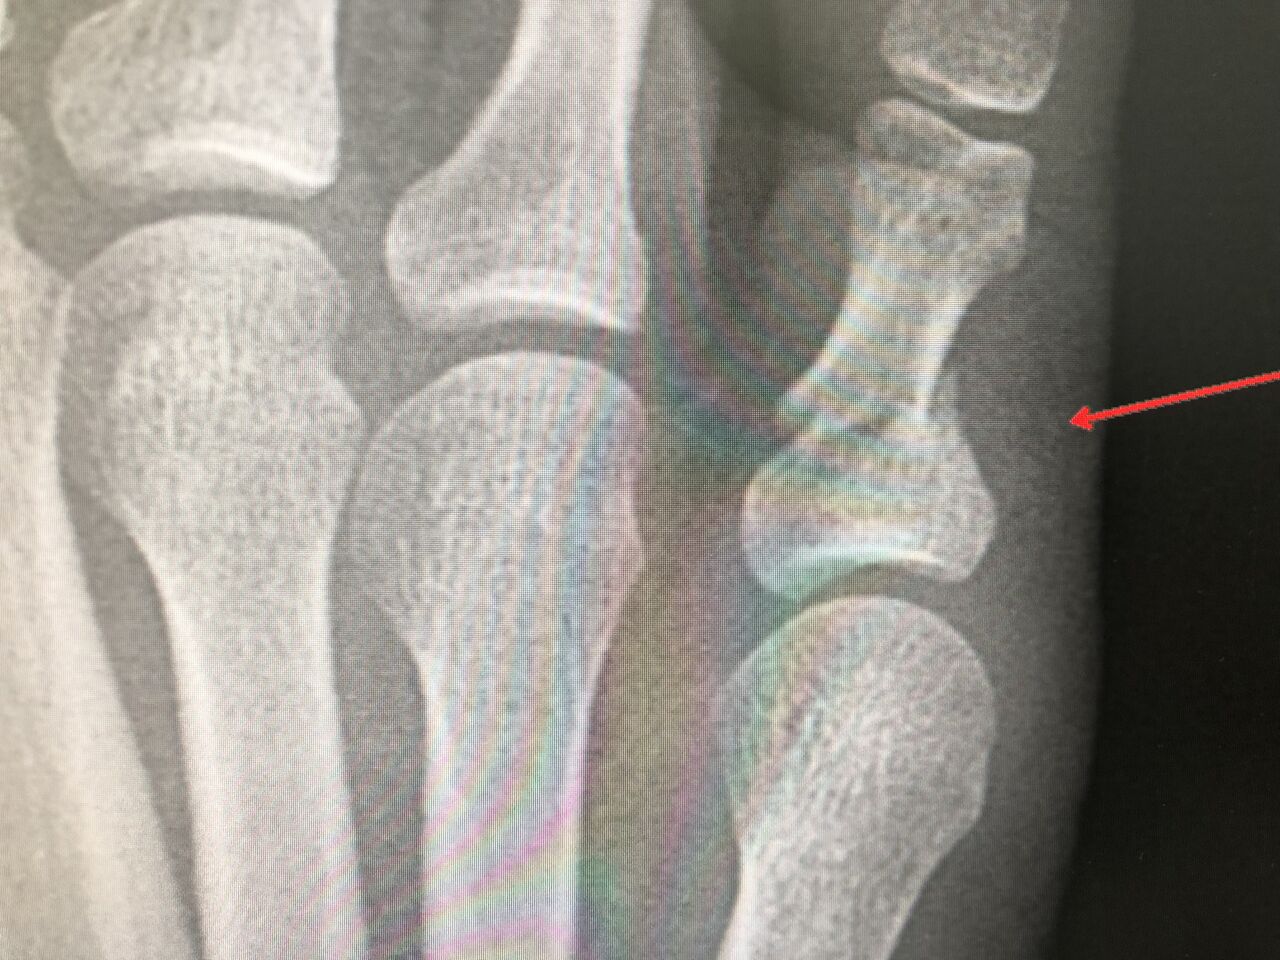

超音波骨治療器(LIPUS)で早期復帰へ

転位骨折が 3週間で骨融合